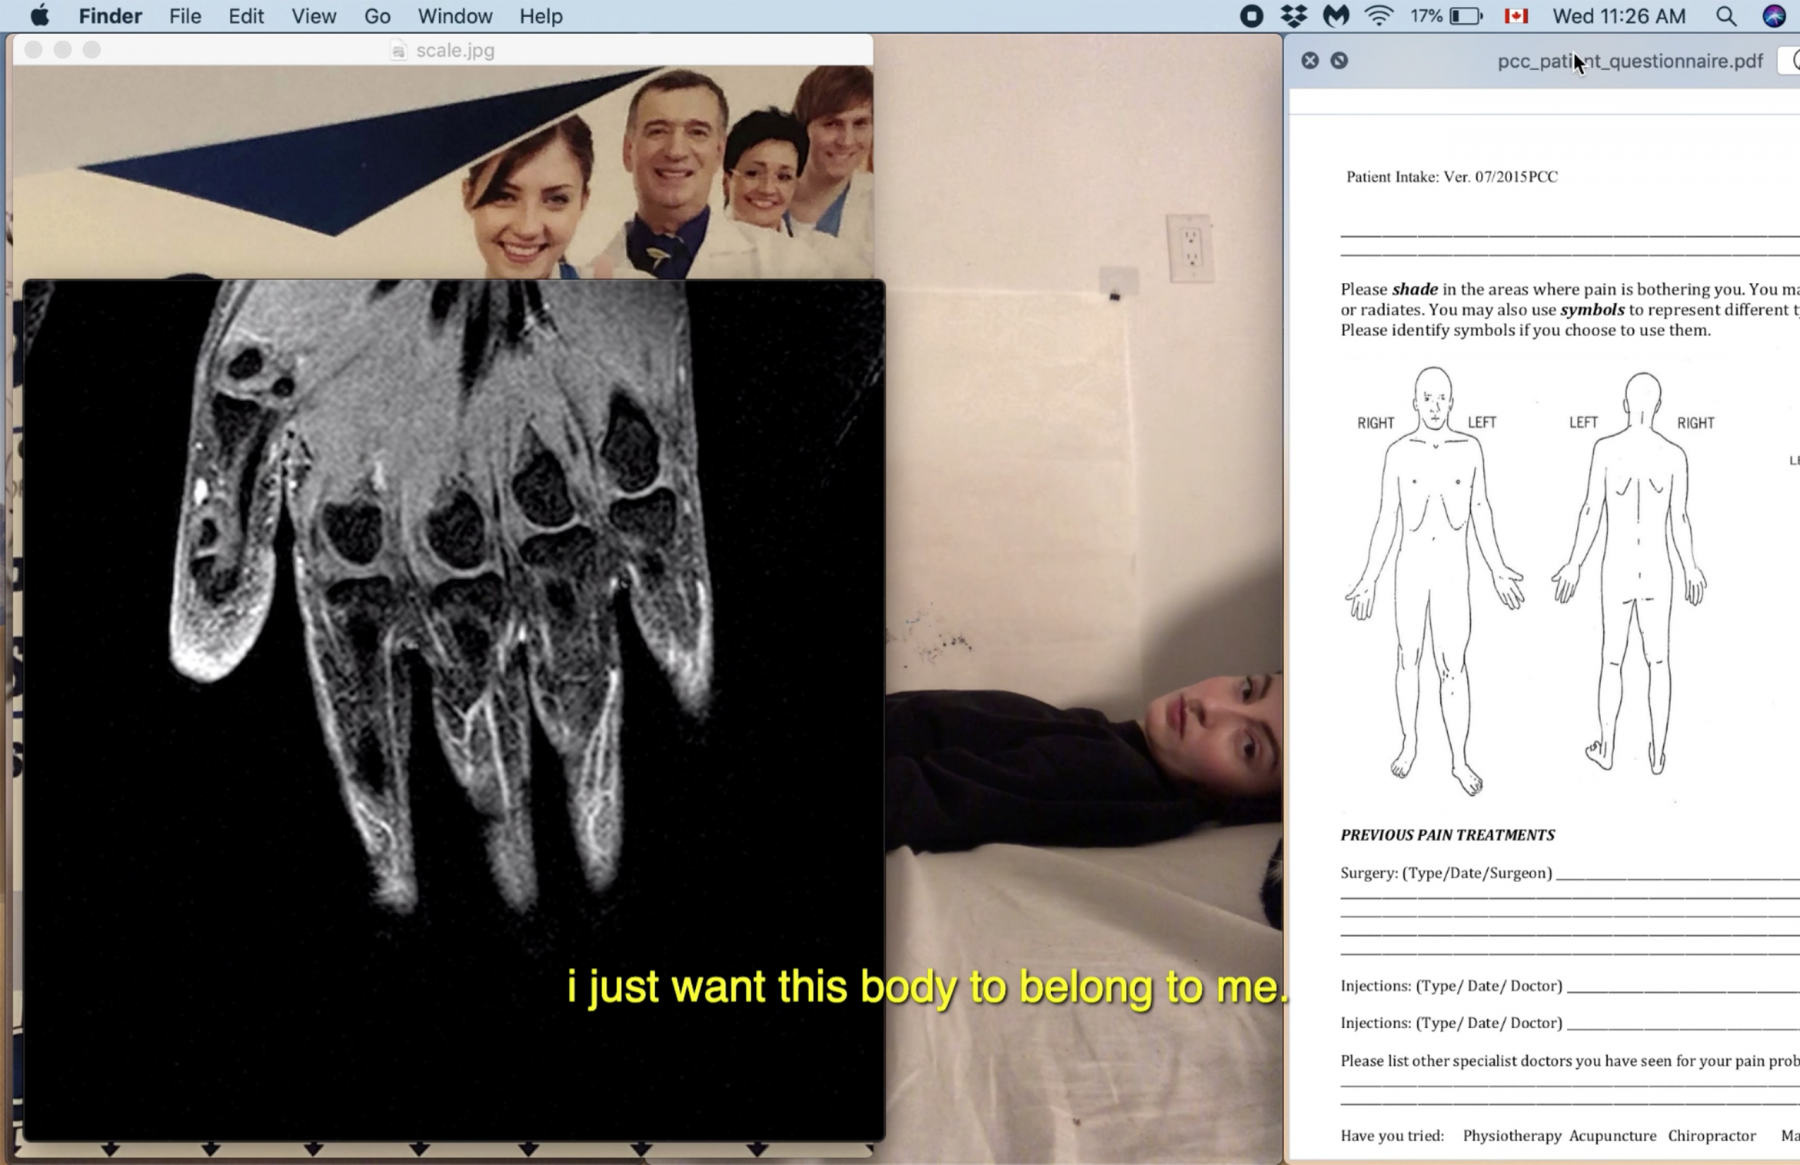

Your recent video 2021-05-17 at 12:48:50 AM (the one that includes “chip thyme”) is a great example of your written and visual practices merging within one work. How did you decide upon this form of the desktop documentary, and what was the process like of making the video?

I was so nervous about making a work that used my writing in this way. Listening to your own voice is hard as fuck [Laughs]. I actually first thought of using desktop recording in our summer course (which was focused on writing). It was all on zoom so I was trying to think of a way to share visuals that referenced the piece of writing I was reading in a way where I wouldn’t have to pull everything up while I was talking. So I just made a desktop recording of me pulling up all the visuals I wanted to share, somewhat in line with the pacing of the writing. It essentially started as a way to calm my nerves for a presentation and avoid the added pressure of multitasking. But it also felt like a really simple way to contextualize the work I was doing, while playing further into this idea of vulnerability. Maybe it’s just me, but every time I have to screen share I feel so exposed. Like suddenly I feel very naked and concerned that something extremely embarrassing or incriminating will be on display. And I think having this video of me sharing my desktop screen, and playing videos of me breathing/drawing in bed, and showing my medical records felt like a way to let the viewer into my private physical space—but also my private digital space. Both the digital space of my laptop and the physical space of my bed have become really essential to my work as tools that make my practice more accessible to me, and I think to the viewer as well.